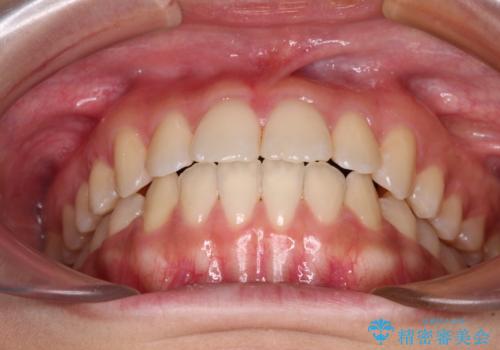

- 上下のデコボコと奥歯の咬みにくさを気にして来院された患者様です。

上顎骨の幅が下顎骨よりも小さく受け口傾向であったため、拡大装置により上顎骨の骨幅を広げて上下関係を改善し、その後インビザラインにて歯並びを整えることとしました。

下顎歯列は上顎歯列内に収まるように並んでいますが、上顎骨の幅が狭いと、下顎臼歯が全体的に舌側に傾斜した歯列となってしまいます。

舌側に傾斜した歯列は奥歯に力の負担がかかりやすく、歯磨きがしにくいなどの問題があるため、上顎骨拡大により舌側傾斜を改善することが可能となります。